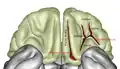

![]() Глазничная поверхность левой лобной доли, типичный рисунок глазничных борозд в виде буквы «H» | |

Снаружи от обонятельной борозды нижняя поверхность лобной доли покрыта изменчивыми по своей форме бороздками, которые чаще всего образуют сочетание в виде буквы «Н» и обозначаются как глазничные (или орбитальные) борозды. Поперечную борозду, обычно образующую перекладину буквы «Н», некоторые авторы называют поперечной глазничной (орбитальной) бороздой (лат. sulcus orbitalis transversus), а отходящие от нее продольные бороздки — латеральной и медиальной глазничными (орбитальными) бороздами (лат. sulci orbitales lateralis et medialis). Между глазничными бороздами располагаются четыре глазничные извилины[1][2].

Количество, форма и рисунок глазничных борозд варьируется у разных людей. Медиальная, латеральная и поперечная глазничные борозды формируют рисунок, напоминающий очертаниями букву «H», «X» или «K». Эти борозды разделяют орбитофронтальную кору на четыре главные извилины: медиальную, латеральную, переднюю и заднюю глазничную (орбитальную) извилину. Есть три основных типа рисунка глазничных борозд, наблюдаемые у людей и у макак; более сложные рисунки наблюдаются только у людей и они связаны с наличием дополнительных глазничных борозд[3]. У пациентов с шизофренией и шизотипическим расстройством обнаружено значительно меньшее число глазничных борозд по сравнению с контрольной группой здоровых людей[4].